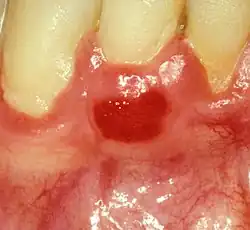

Plasma cell gingivitis in 7-year-old child. Histologically verified.

Plasma cell gingivitis in a 10-year-old child. Histologically verified.

Plasma cell gingivitis appears as mild gingival enlargement and may extend from the free marginal gingiva on to the attached gingiva.[6] Sometimes it is blended with a marginal, plaque induced gingivitis, or it does not involve the free marginal gingiva. It may also be found as a solitude red area within the attached gingiva (pictures). In some cases the healing of a plaque-induced gingivitis or a periodontitis resolves a plasma cell gingivitis situated a few mm from the earlier plaque-infected marginal gingiva. In case of one or few solitary areas of plasma cell gingivitis, no symptoms are reported from the patient. Most often solitary entities are therefore found by the dentist.[2]

The gums are red, friable, or sometimes granular, and sometimes bleed easily if traumatised.[6] The normal stippling is lost.[7] There is not usually any loss of periodontal attachment.[6] In a few cases a sore mouth can develop, and if so pain is sometimes made worse by toothpastes, or hot or spicy food.[7] The lesions can extend to involve the palate.[7]